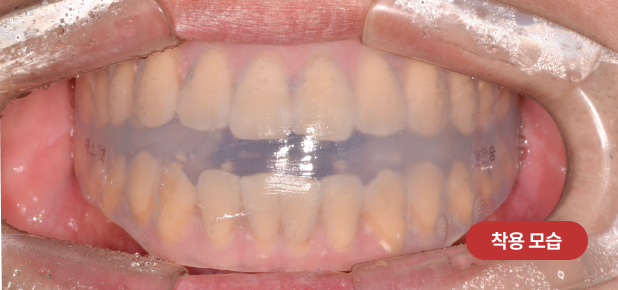

치과교정과전문의가 연구, 개발하고 특허받은 코골이 장치는

부드러운 소프트 재질로 보다 편안한 착용이 가능하며,

코골이 및 수면무호흡 완화, 피로 개선, 구호흡 개선이 가능합니다.